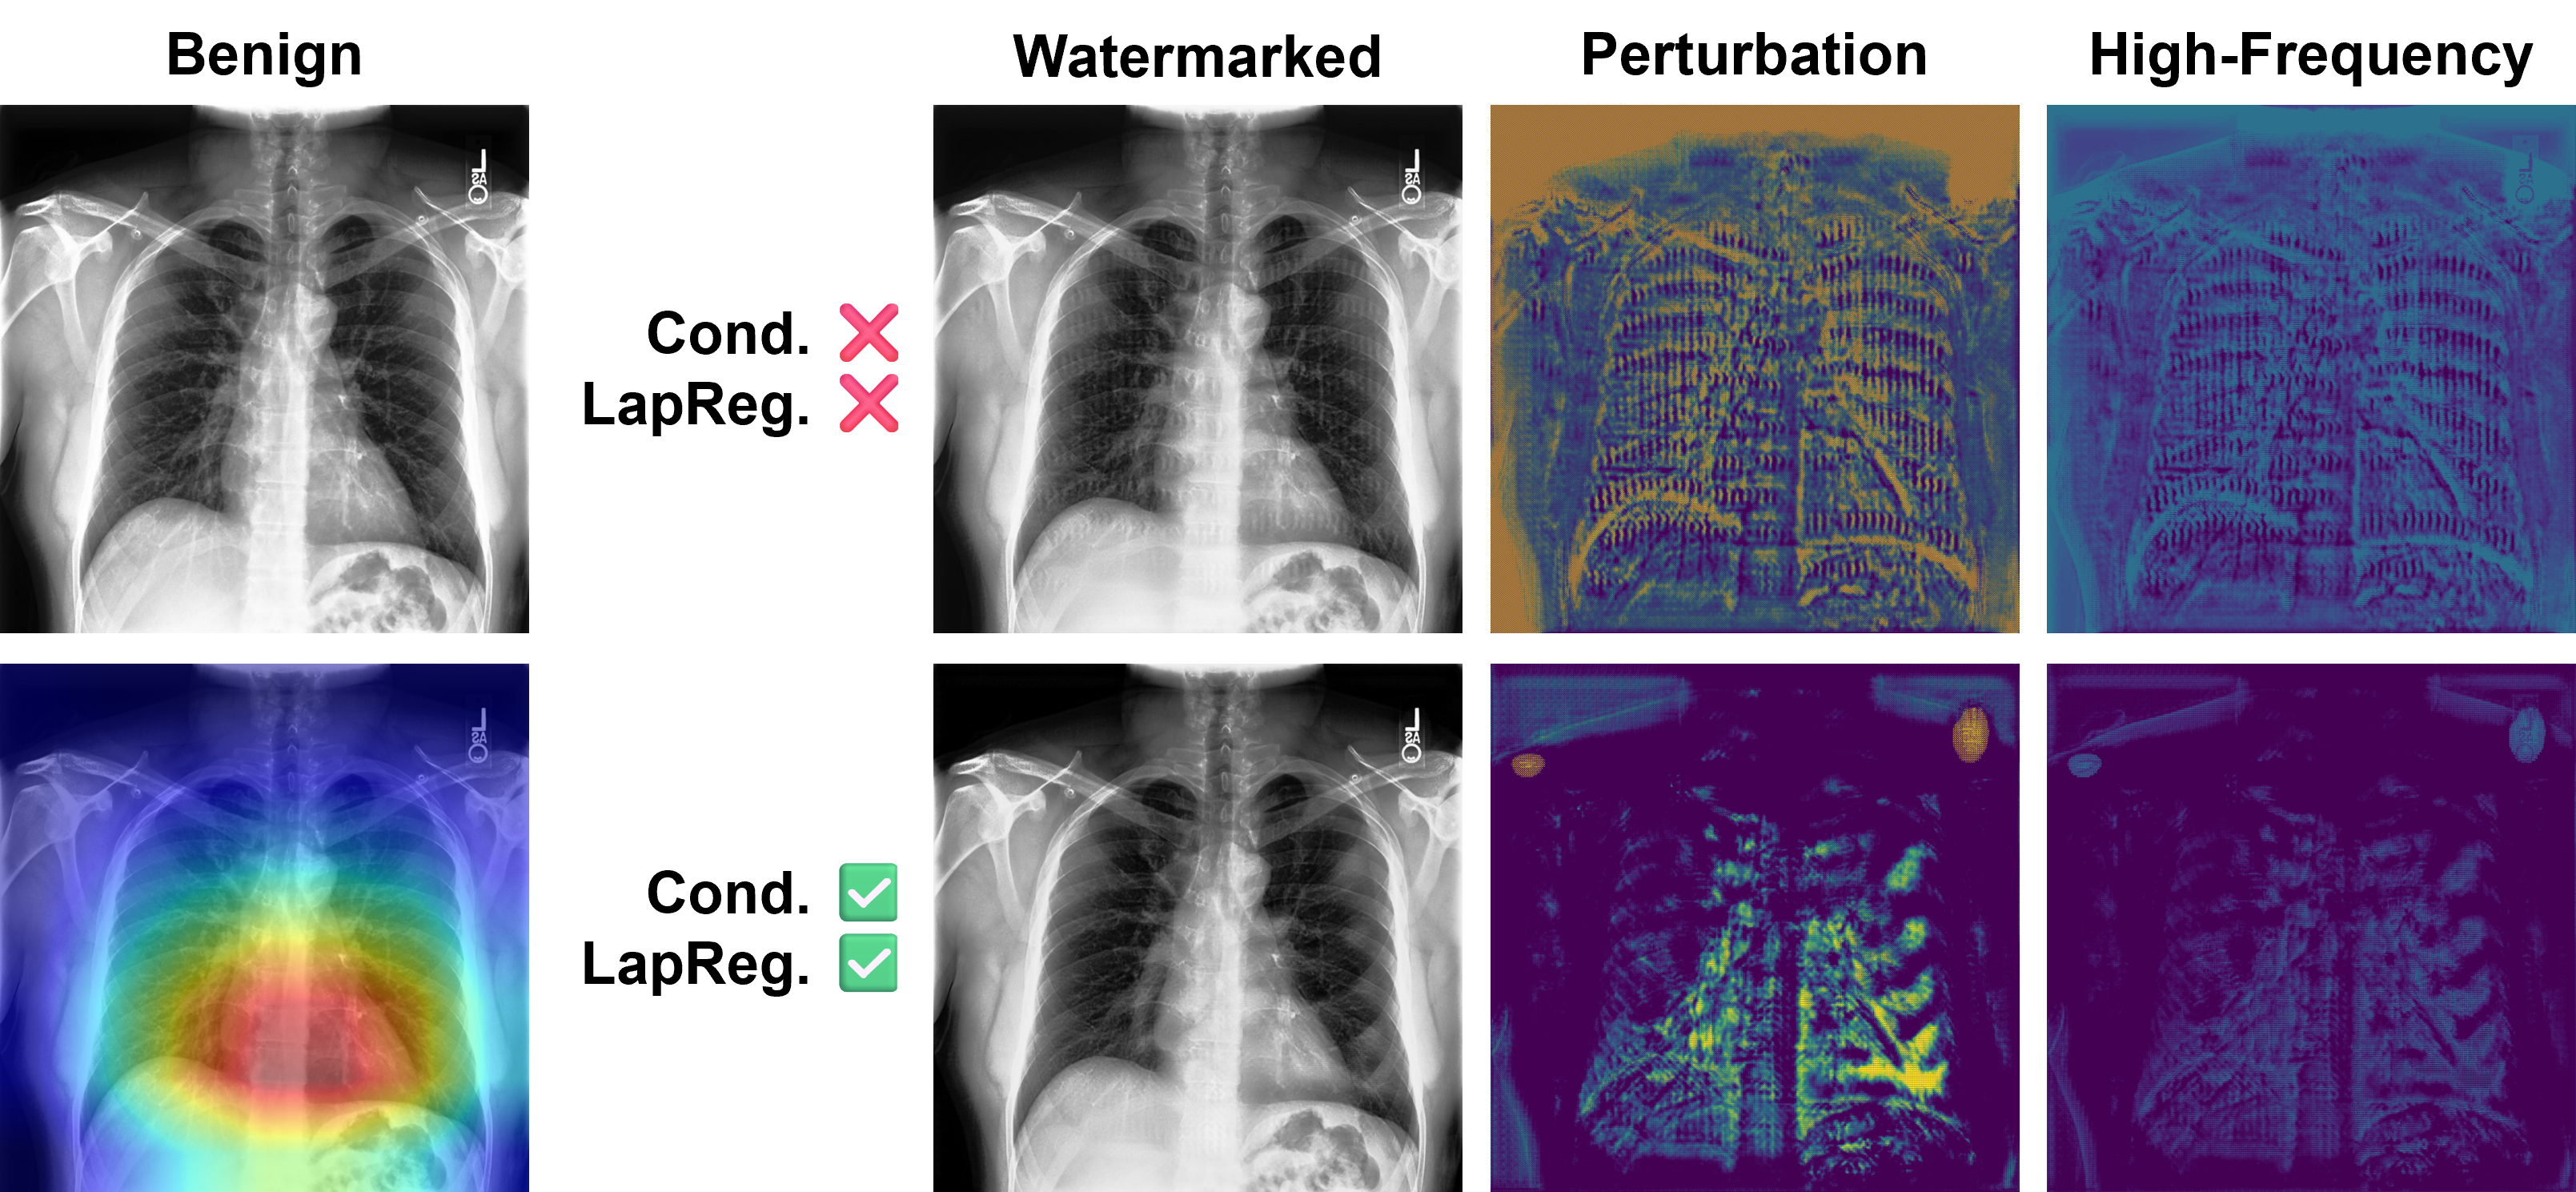

Impact of Saliency Conditioning

To study the impact of saliency conditioning, we train watermark generators G(;θ)G(\cdot;\theta) with and without the EigenCAM-based saliency conditioning module. As shown in Table 3, dataset watermarking performance is not affected by saliency conditioning, with comparable BA, WSR, and LPIPS metrics across both settings. We observe a decrease in Lap\mathcal{L}_{\text{Lap}} even when Laplacian regularization is not applied, likely due to the perturbations being concentrated within salient regions of the image. This behavior is visualized in Figure 5.

Impact of Laplacian Regularization

To study the impact of Laplacian regularization, we train watermark generators G(;θ)G(\cdot;\theta) with and without the Laplacian pyramid loss Lap\mathcal{L}_{\text{Lap}} in the training objective. As shown in Table 3, we observe an increase in BA (4%\sim 4\%) and decrease in Lap\mathcal{L}_{\text{Lap}}, while WSR and LPIPS remain unchanged. This indicates that Laplacian regularization mitigates high-frequency perturbations. We visualize the high-frequency information using the Laplacian filter 2\nabla^{2} (i.e., high-pass filter) in Figure 5.

Refer to caption

Figure 5: An example illustrating the impact of EigenCAM-based saliency conditioning and Laplacian regularization.